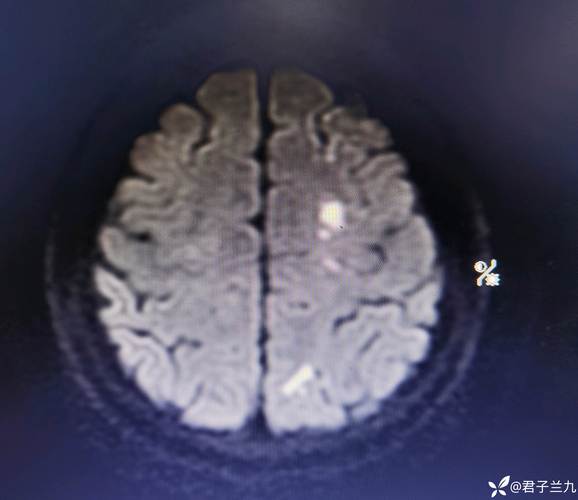

- 腔梗灶:这是“缺血性脑卒中”的一种特殊类型,全称是“腔隙性脑梗死”,它是由大脑深部的一些非常细小的动脉(穿通支)堵塞引起的,因为这些动脉很细,堵塞后坏死的脑组织范围也很小,形成一个像“小洞”或“小腔”一样的病灶,所以叫“腔隙性”梗死。

一句话总结: “脑内多发缺血及腔梗灶”意味着,在大脑的深部区域,存在多个由小血管堵塞或长期供血不足引起的小梗死灶。 它是脑小血管病的一种表现,通常与长期的高血压、糖尿病、高血脂等慢性病有关。

很多腔梗灶非常小,位于大脑的“静区”(非功能区),因此不会引起任何明显的临床症状,很多人是在体检做头颅CT或MRI时偶然发现的。